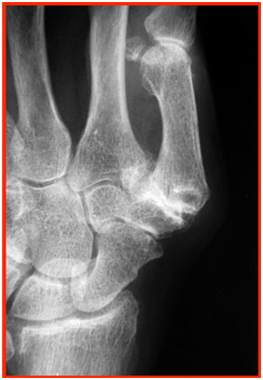

This is an inflammatory arthropathy, affecting multiple joints.

These patients usually have multiple joint deformity, involving the metacarpophalangeal joints, interphalangeal joints, carpometacarpal joint, distal radio-ulnar joints, wrist and carpal joints. This results in limited motion as a result of the joint destruction.

Complications can also arise as a result of the underlying rheumatoid arthritis. Examples include tendon rupture, joint degeneration and joint subluxation.